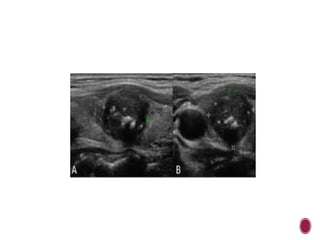

PAPILLARY CARCINOMA

 Papillary carcinoma with

typical features:

 a- hypo-

echogenicity ,macrocalcifica

tions

 b-hypervascularity with

chaotic arrangement